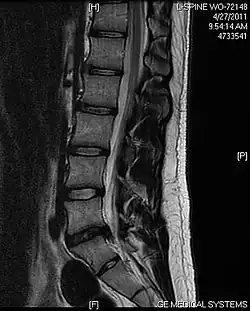

L'imagerie par résonance magnétique peut montrer la hernie, le canal vertébral, les nerfs, les tissus environnants. Les tissus mous sont les mieux analysés par cet examen qui est le plus performant pour le diagnostic de hernie discale. Les images pondérées en T2 montrent clairement la hernie.

IRM cervicale sagittale montrant une hernie discale de niveau C5-C6.

IRM cervicale sagittale montrant une hernie discale de niveau C6-C7.